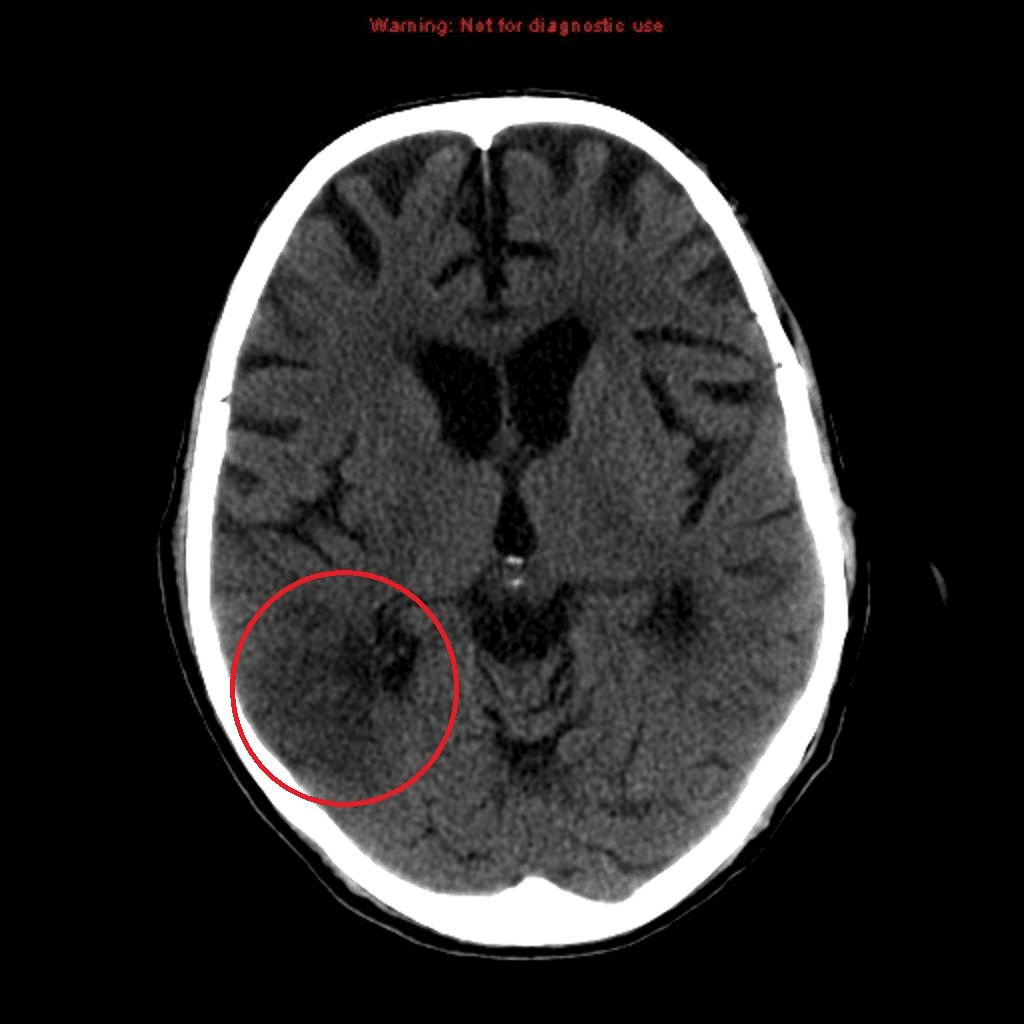

9. Question

9. A patient’s stroke symptoms began 2 hours ago. In the emergency department, she has the following CT scan of the head:

What is the next most appropriate step?